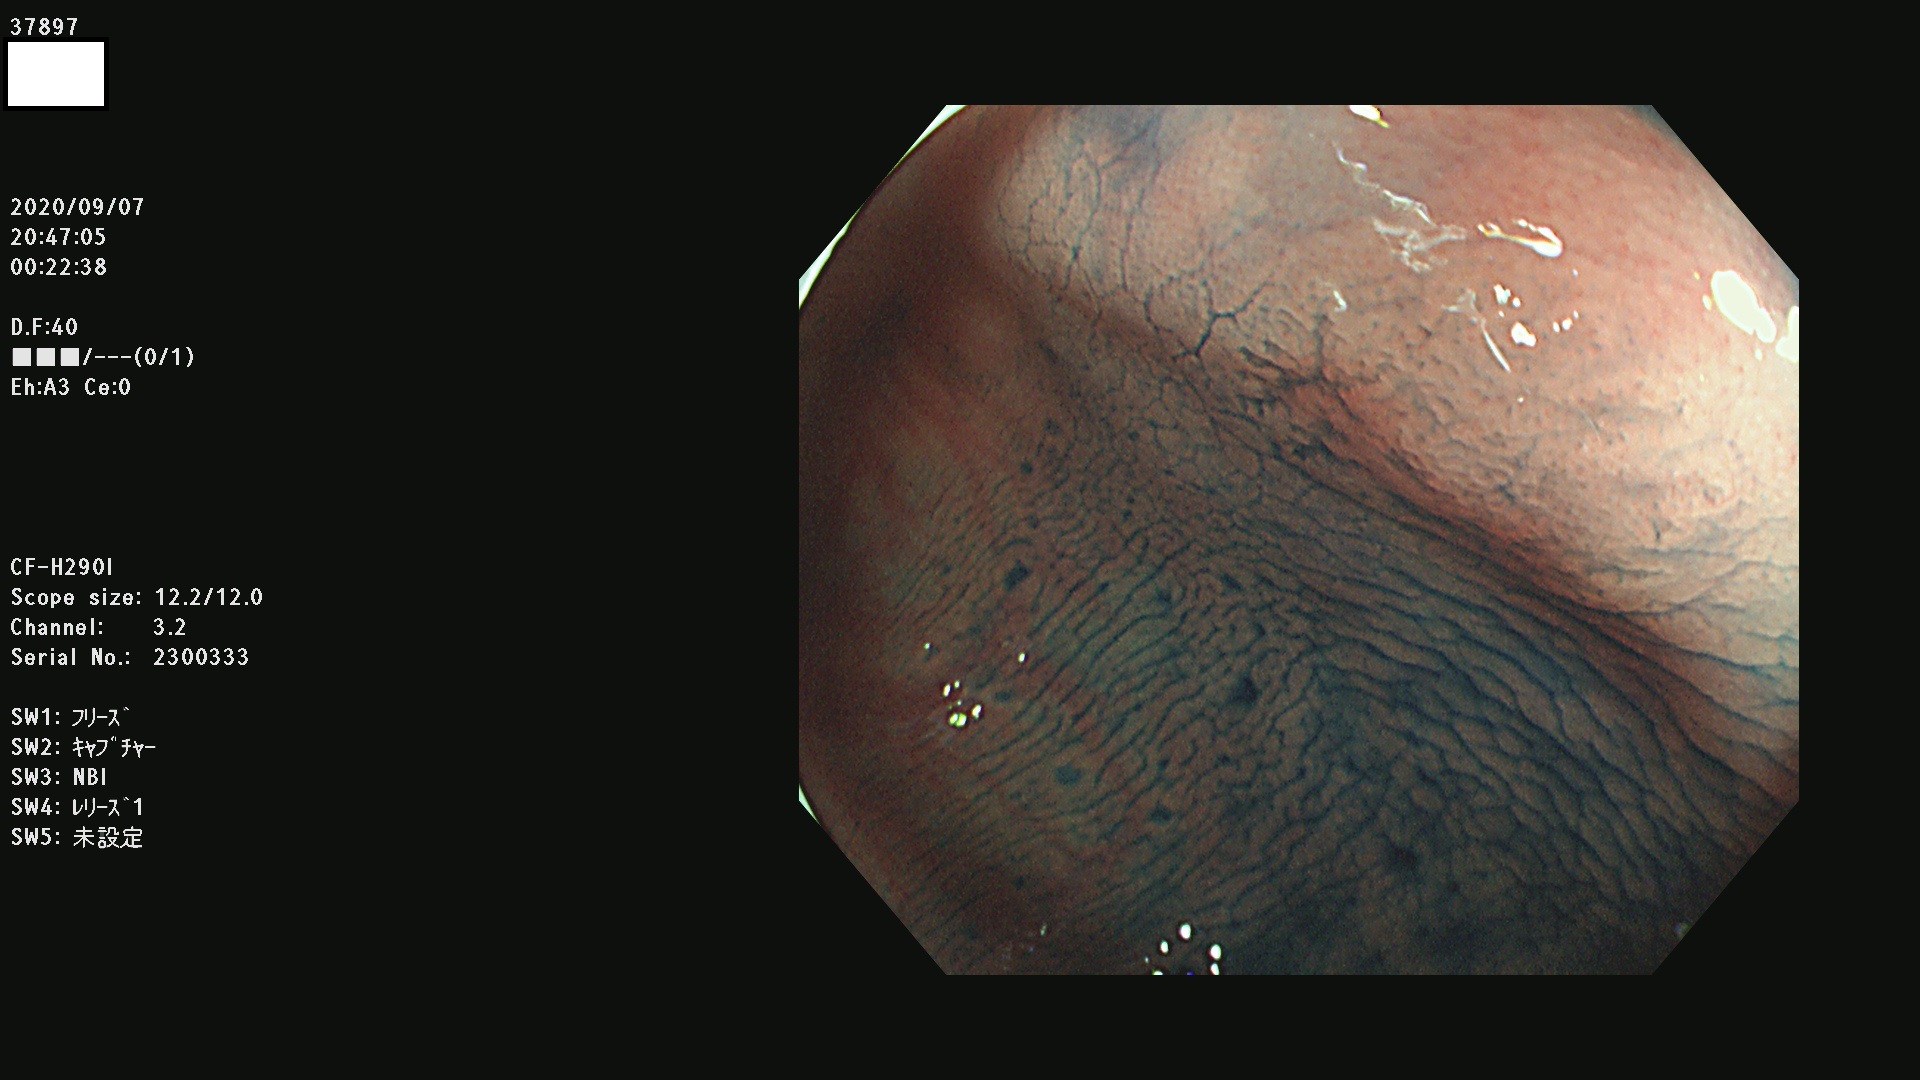

腺腫発見率 75 % (カルテ番号 37800〜37899の100名の方の検査結果で集計)大腸癌検診最新情報

以下のカルテ番号の方に腺腫(Adenoma,Group3〜5)が見つかりました(集計法)

37800(SSAPのみ) 37801 37802 37803 37804 37805 37806 37807 37808 37809(SSAPのみ) 37810 37811 37812 37813 37814 37815 37817 37818 37819 37820 37821 37822 37824 37825 37826 37827 37828 37829 37832 37833 37836 37837(SSAPのみ) 37839 37840 37842 37844 37845(SSAPのみ) 37847 37849 37850 37851 37852 37853(SSAPのみ) 37855 37856 37857 37860 37861 37862 37863 37864 37867 37868 37871 37874 37876 37877 37879 37880 37881 37882 37883 37886 37887 37888 37889 37890 37891 37892 37893 37894 37896 37897 37898 37899

発見困難で危険性の高い平坦型病変(上記100名より抽出) ![]()